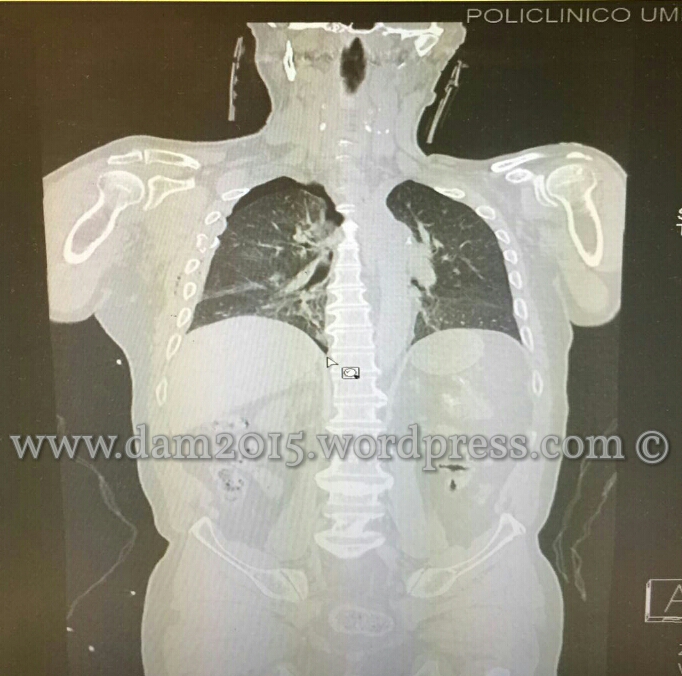

Si esegue TC total body:

-TORACE, discreta falda di pneumotorace destro con parziale collasso del polmone e lieve sbandieramento controlaterale del mediastino. Frattura pluriframmentaria dell’arco antero-laterale della III-IV-V-VI-VII costa di destra. Frattura pluriframmentaria e parzialmente scomposta della scapola di destra.